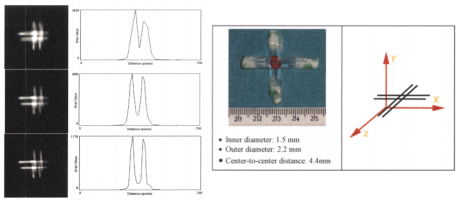

| JOURNAL | IEEE Nuclear Science Symposium & Medical Imaging Conference, 2015 |

| ABSTRACT | When multiple pinholes are used to acquire SPECT projection data, there may be regions on the detectors where data from two or more pinholes overlap. Such “multiplexing” of projection data can cause artifacts and/or increased noise in reconstructed SPECT images, depending on the exact acquisition geometry. We previously described a modified MLEM algorithm that alternates between (i) estimating the separated projection data that would be obtained through each individual pinhole (i.e., demultiplexed data), based on the current MLEM iteration’s image, and (ii) reconstructing the SPECT image by MLEM, but assuming that the demultiplexed data estimates are the actual measured data. The modified MLEM algorithm was first tested with data simulated for a stationary 39pinhole collimator tube, and more recently with Tc99m phantom data acquired from three vials of different sizes on a 6pinhole, tripledetector SPECT camera. |